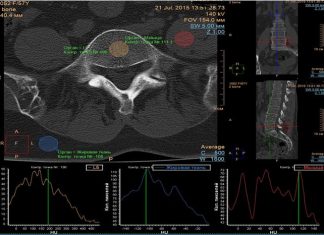

КТ-Денситометрия Костей: Современные Технологии в Диагностике Остеопороза

В мире медицинских технологий появляются инновации, направленные на раннюю диагностику и эффективное лечение заболеваний опорно-двигательной системы. Одной из передовых методик является компьютерная томография с...